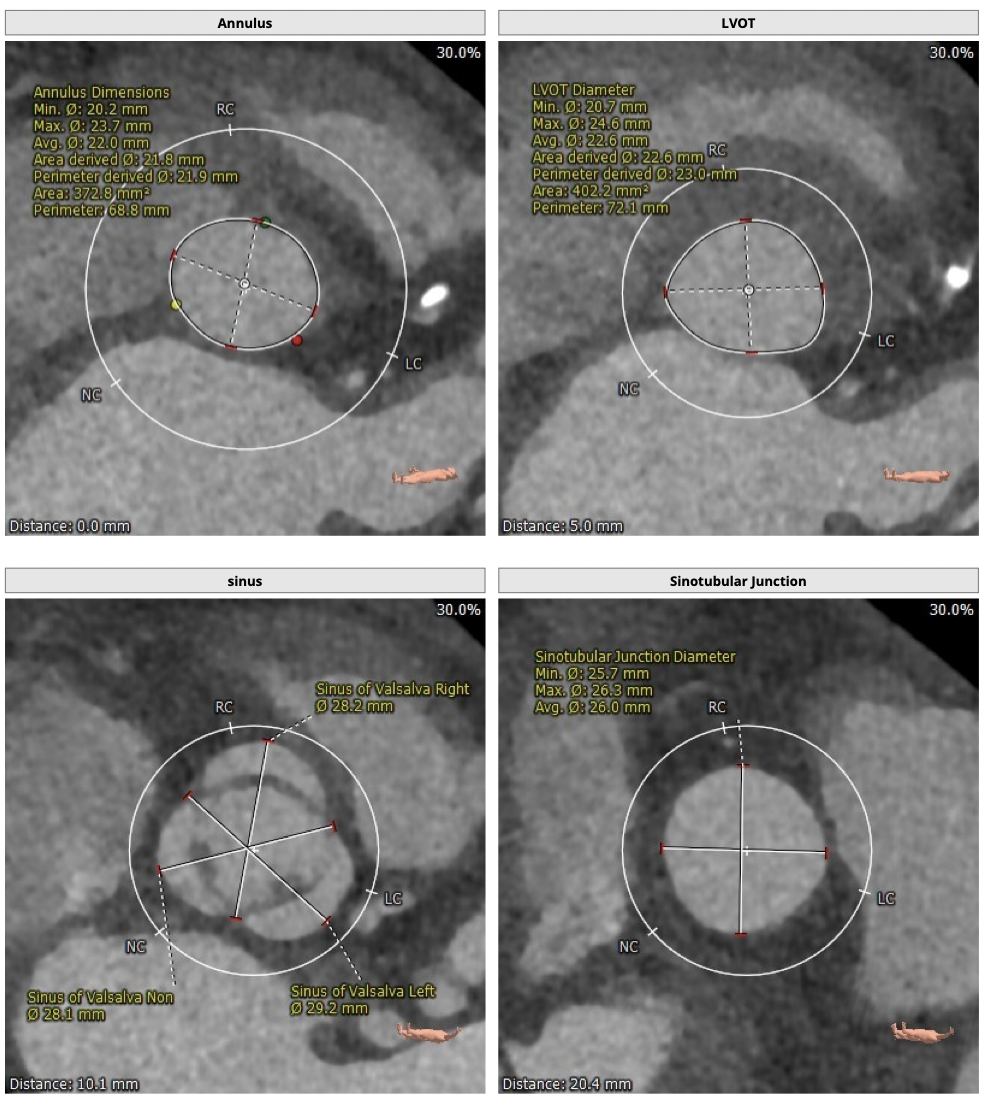

CT检查

图片